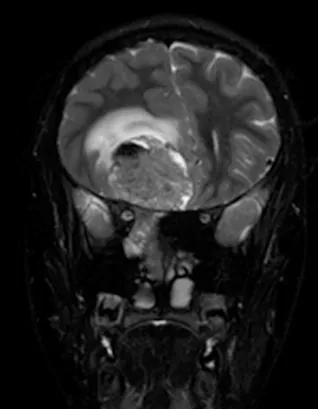

一名15岁、既往健康的男性,因额部头痛加剧、恶心、呕吐和疲劳两周病史就诊。家属注意到在就诊前一个月出现言语失控和非典型行为。他的神经系统检查显示双侧视乳头水肿,无其他局灶性缺损。所有血液检查均正常,血清生殖细胞肿瘤标志物也为阴性。脑和鼻旁窦的计算机断层扫描(CT)和磁共振成像(MRI)扫描显示,右侧有一个5.5 x 4.4 x 5.6厘米的肿块,起源于鼻腔、筛窦和蝶窦。它已侵蚀筛板进入前颅窝。该肿块在CT扫描上未钙化(图1),与脑组织等密度,伴有不均匀的对比增强。该肿块在T1和T2加权MR图像上(图2、3、4)与脑组织等信号,并在钆增强后显示不均匀强化。注意到周围有血管源性脑水肿和占位效应。脊柱MRI未见转移证据。

图4:冠状位T2加权MRI扫描,证实了颅内肿瘤成分的不均匀实性和囊性性质。病灶周围水肿以及肿瘤相关的中线移位也清晰可见。